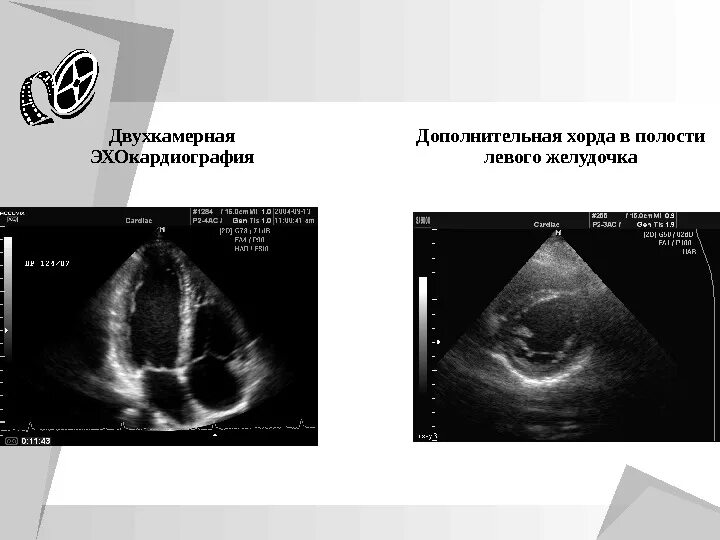

Дополнительная хорда мкб